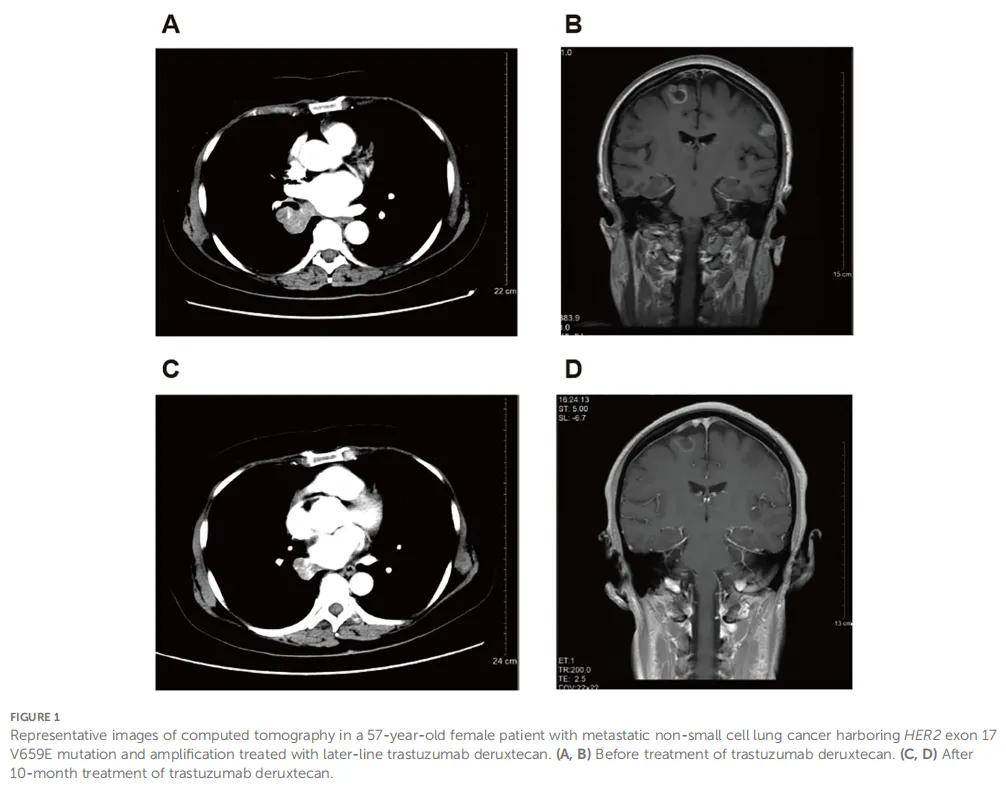

患者女,57 岁,因严重肩痛于 2020 年 5 月入院。该患者于 2019 年 7 月被诊断为右下叶肺腺癌,伴纵隔淋巴结、肝及骨转移。当时患者拒绝治疗。基因检测显示无表皮生长因子受体(EGFR)、间变性淋巴瘤激酶(ALK)或ROS原癌基因1(ROS1)突变,程序性死亡配体1(PD-L1)肿瘤比例评分(TPS)为 3%。本次入院时,影像学检查显示肿瘤进展至右肺中叶并扩散至脑。疾病分期为cT4N2M1c。患者自 2020 年 5 月起接受替雷利珠单抗(200 mg,第 1 天)联合培美曲塞(750 mg,第 1 天)、卡铂(400 mg,第1天)及贝伐珠单抗(600 mg,第 1 天)治疗,共 6 个 21 天周期,但拒绝脑及骨病变的局部放疗。2020 年 11 月,计算机断层扫描(CT)和磁共振成像(MRI)显示部分缓解(PR)。随后她接受替雷利珠单抗(200 mg,第 1 天)联合贝伐珠单抗(400 mg,第1天)维持治疗。2021 年 5 月,CT显示肺部病灶进展,肝及脑病灶稳定。她继续接受替雷利珠单抗联合贝伐珠单抗治疗,另加白蛋白结合型紫杉醇(400 mg,第1天)和卡铂(400 mg,第 1 天),共 4 个周期。2021 年 9 月,CT显示肺部病灶达到PR,肝及脑病灶稳定。随后她接受替雷利珠单抗联合贝伐珠单抗及长春瑞滨(40 mg,每周第1、3、5天)维持治疗直至 2023 年 3 月,之后接受贝伐珠单抗(300 mg,第 1 天)联合长春瑞滨(40 mg,每周第 1、3、5天)治疗。2023 年 6 月,CT显示疾病进展。长春瑞滨换为吉西他滨(1400 mg,第1、8天)联合顺铂(90 mg,第1天),同时继续贝伐珠单抗治疗。2023 年 8 月,CT和MRI显示肺及脑病灶稳定(图1A、B)。活检显示患者为微卫星稳定、PD-L1阴性,伴HER2突变(17外显子V659E)和HER2扩增。随后开始接受德曲妥珠单抗(5.4 mg/kg,每 3 周一次)单药治疗。2024 年 6 月达到PR(图1C、D),并持续至末次随访日期(2024 年 9 月)。德曲妥珠单抗治疗期间出现恶心、呕吐、肌酐升高、白细胞计数降低及肝酶升高,均为 1-2 级,经对症治疗可控制。

▲图1 患者代表性CT影像